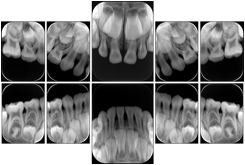

Intra-oral radiography typically involves acquisition of multiple images of various parts of the dentition. Many digital radiographic systems offer customized templates that are used for displaying the images in a study on the screen. These templates may also be referred to as mounts or view sets. The Structured Display Object represents a standard method of encoding and exchanging the layout and intended display of Structured Displays. A structured display object created in this manner could be stored with a study and exchanged with images to allow for complete reproduction of the original exam.

2. A patient requests cosmetic surgery to enhance their facial appearance. The case requires consultation between an orthodontist in New York and an oral surgeon in California. The cephalometric series of 2D projections constructed from a volumetric CT data set that is used for the discussion is arranged by a Structured Display for transfer between the two practitioners.

Cephalometric Series Structured Display

Figure OO-2. Cephalometric Series Structured Display

3. A dental provider wishes to capture a series of DICOM IO images for the patient’s dentition. The tooth morphology, teeth are divided into molars, premolars, canines and incisors, and a number of images for each jaw. The anatomic information was captured utilizing the triplet of schema. This standard code sequence is based on ISO 3950-2010, Dentistry - Designation system for teeth and areas of the oral cavity.

In most standard cases, images are oriented in structured layouts. These structured displays are useful to be shared between providers for reference purposes.

Table OO.1.1-1 shows structured display standard templates, where Viewset ID is based on the Japanese Society for Oral and Maxillofacial Radiology (JSOMR) classification provided by JIRA (Japan Medical Imaging and Radiological Systems Industries Association, www.jira-net.or.jp). Expected or typical teeth to be imaged location, region and designation codes are based on ISO 3950-2010, Dentistry - Designation system for teeth and areas of the oral cavity. For all the hanging protocols listed in OO.1.1-1, the value to use for Hanging Protocol Creator (0072,0008) is "JSOMR" and the value to use for Hanging Protocol Name (0072,0002) does not include "JSOMR" (e.g., "DL-S001A", not "JSOMR DL-S001A").